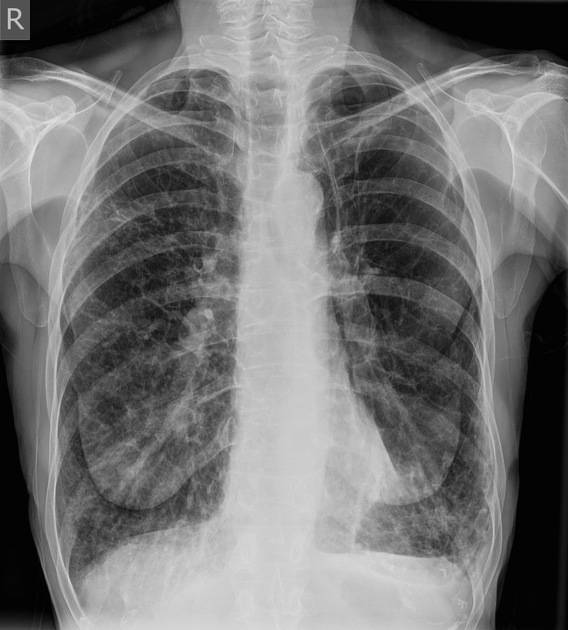

Исследование проводится в прямой и боковой проекциях грудной клетки с возможным выполнением прицельной съёмки корней лёгких. Визуализируются преимущественно косвенные признаки: усиление и деформация лёгочного рисунка, признаки гиповентиляции, гиперинфляции и утолщения бронхиальных стенок. Цель исследования — подтверждение наличия бронхиальной обструкции, оценка степени вовлечения бронхиального дерева и исключение очаговой или инфильтративной патологии.

Рентгенография выявляет следующие признаки обструктивного бронхита:

Усиление и неравномерная деформация сосудисто-бронхиального рисунка, преимущественно в прикорневых и среднедолевых отделах.

Утолщение стенок бронхов с кольцевидными и линейными затемнениями на фоне повышенной воздушности лёгочной ткани.

Гиперинфляция лёгких с увеличением объёма грудной клетки, опущением и уплощением куполов диафрагмы.

Снижение прозрачности прикорневой зоны за счёт воспалительного перибронхиального инфильтрата.

Умеренное расширение просвета крупных бронхов и признаки воздушной ловушки в периферических отделах.

Нарушение архитектоники легочного поля с локальными участками гиповентиляции без инфильтративной тени.